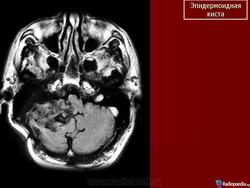

Эпидермоидная киста

Эпидермоидная киста.